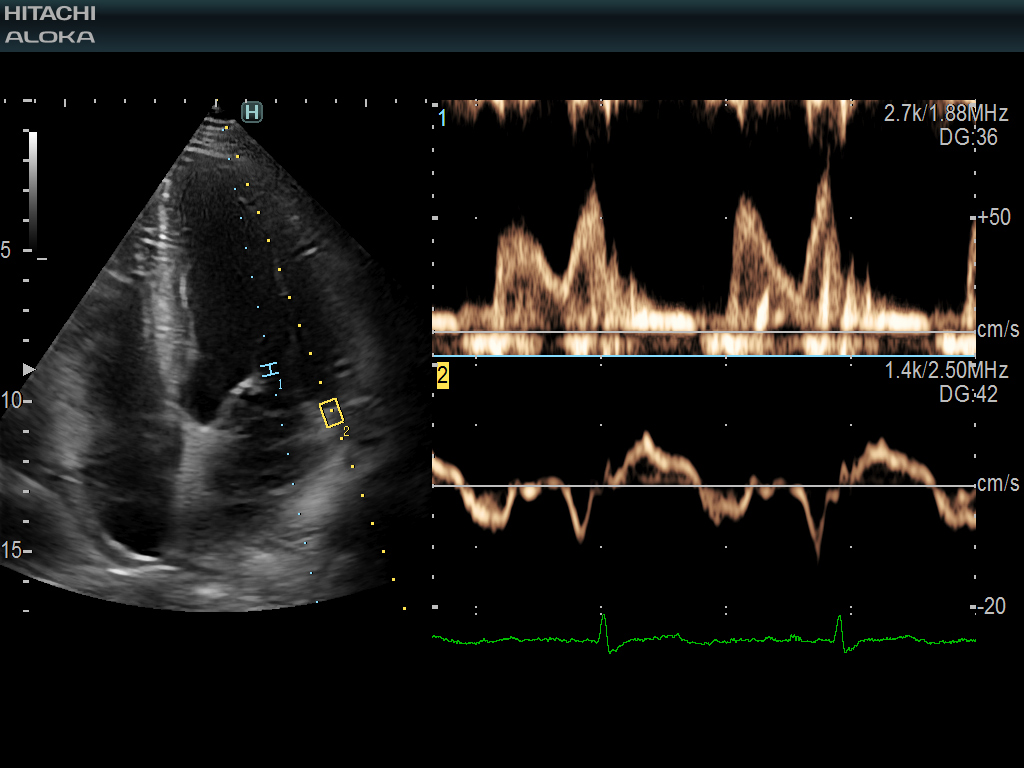

혈류와 조직 도플러 파형의 조합은 LV 이완기 성능 지표 및 E / e '비율과 같은 동일한 청취 비트 측정 동안 허용합니다.